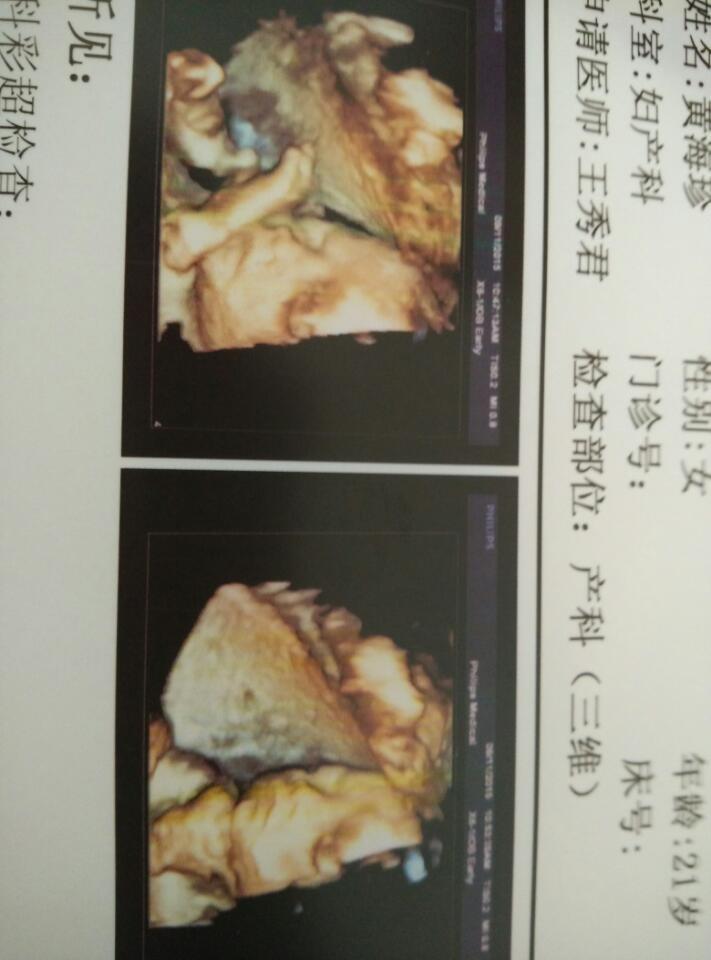

怀孕24周加6天?宝宝?我三维和糖耐通过了?宝妈们?帮我看一下宝宝是女孩还是男孩呢